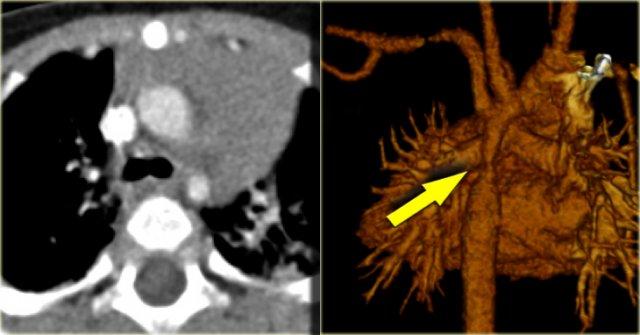

On the left a patient with a right arch with an aberrant left subclavian (indicated by the yellow arrow).

There is a right arch and the left subclavian artery is the last branch of the aortic arch, indicating that this is an aberrant left subclavian.

Medially to the left subclavian artery we see the left common carotid, that originates from the right side and has an oblique course to the left.

Same patient.

Posterior oblique view of volume rendered image to show the aberrant left subclavian artery.